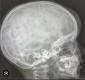

: CRANEO normal

: CRANEOSINOSTOSIS